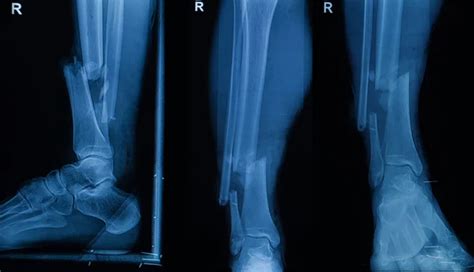

Okay, before we get into the nitty-gritty of ICD-10 codes, let’s quickly review the common foot bones and fracture types . The foot is a complex structure composed of 26 bones, divided into three main sections: the forefoot, midfoot, and hindfoot. The forefoot consists of the metatarsals and phalanges (toes), the midfoot includes the cuneiforms, navicular, and cuboid bones, and the hindfoot is made up of the talus and calcaneus (heel bone). Fractures in any of these bones can be quite painful and debilitating, affecting mobility and quality of life. Common types of foot fractures include metatarsal fractures, which are often seen in athletes or individuals who engage in high-impact activities. These fractures can occur due to direct trauma, overuse, or stress. Phalangeal fractures, or toe fractures, are also common and can result from stubbing the toe or dropping a heavy object on the foot. Midfoot fractures, such as those involving the navicular or cuneiform bones, are less frequent but can be more complex and may require surgical intervention.

Hindfoot fractures, particularly calcaneal fractures, are often caused by high-energy injuries like falls from a height or motor vehicle accidents. These fractures can be severe and may involve significant soft tissue damage. Another important type of foot fracture is a stress fracture, which is a small crack in the bone that develops over time due to repetitive stress or overuse. Stress fractures are commonly seen in runners, dancers, and military personnel. They typically occur in the metatarsals but can also affect other bones in the foot. When classifying foot fractures, it’s important to consider several factors, including the location of the fracture, the type of fracture (e.g., transverse, oblique, spiral, comminuted), and whether the fracture is open or closed. An open fracture, also known as a compound fracture, involves a break in the skin that exposes the bone to the outside environment, increasing the risk of infection. A closed fracture, on the other hand, does not involve a break in the skin. Additionally, fractures can be displaced, meaning the bone fragments are misaligned, or non-displaced, meaning the bone fragments are still in their normal alignment. Understanding these different types of foot fractures and the specific bones involved is crucial for accurate diagnosis and treatment planning. It also lays the groundwork for correctly assigning the appropriate ICD-10 codes, which we’ll delve into next.